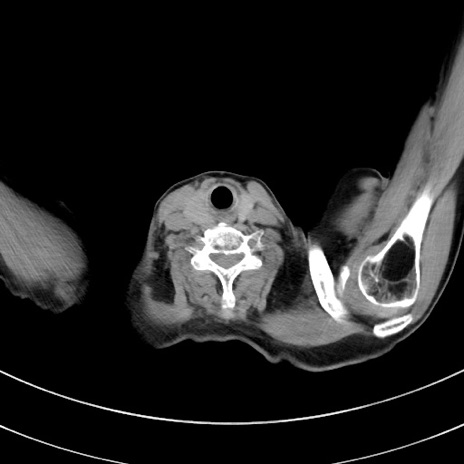

冠状断像